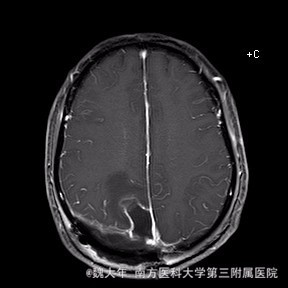

行“右顶开颅右顶部矢状窦旁脑膜瘤切除术”。取右顶马蹄形手术切口 ,颞侧翻开皮瓣,电刀切开骨膜,中线矢状缝上前、后极各钻一孔,颞侧后方钻一孔,铣刀铣一长方形(7*6cm)骨瓣,见硬膜表面较多点状渗血,予充分止血,悬吊硬膜。 显微镜下切除肿瘤:沿肿瘤边缘剪开硬膜后,见一大小约5*5*6cm肿瘤,沿硬膜内侧面呈匍匐状生长,边界与脑组织有蛛网膜分隔,质地较韧,基底与矢状窦关系密切,靠内侧与大脑镰粘连紧密,血供丰富。仔细分离肿瘤与脑组织的粘连,全切除肿瘤。肿瘤基底与矢窦粘连紧密,并破坏矢状窦侧壁,予低功率电刀反复烧灼,直至肿瘤无明显血供表现。严密止血后常规关颅。

术后1周复查头颅MR未见明显肿瘤残留,拆线后出院。